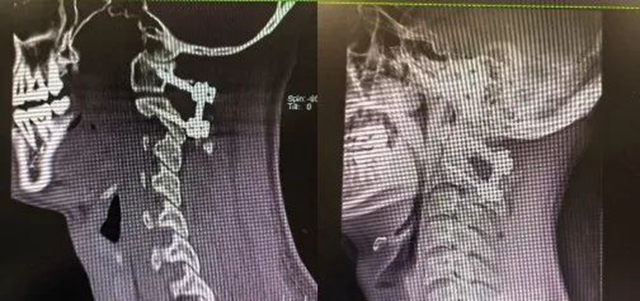

祸从天降! 一根大树枝穿脖而入 医生施妙手转危为安

近日,家住宜宾某县的李家林(化名)爬上树砍柴时不慎坠落,被一根直径约5厘米、长约50厘米的粗大树枝穿入脖子,情况十分危险。   家人紧急将李先生送到西南医科大学附属医院康健中心院区急诊医学部,几位医生联手为其实施了3小时手术,树枝被成功取...